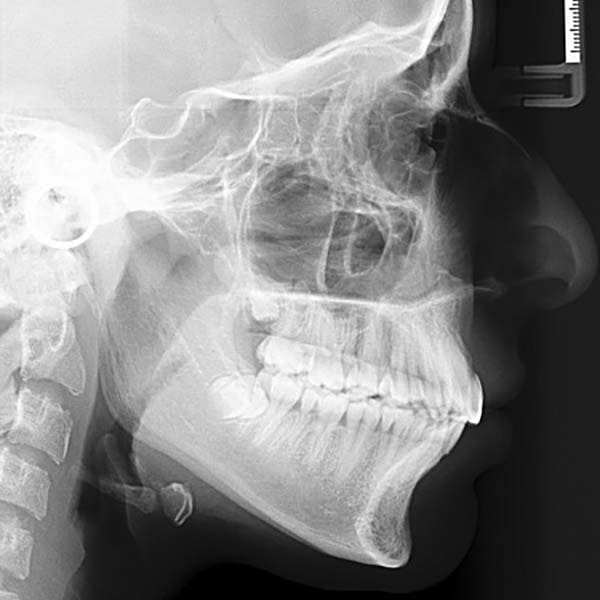

عانت هذه الفتاة الصغيرة من بروز شديد في الأسنان وصل إلى 1 سم، وكان سببه الرئيسي هو تراجع الفك السفلي، وهو ما كان يظهر بوضوح على بروفيل وجهها الجانبي.

تم العلاج على مرحلتين لاستغلال فترة النمو:

كما تظهر الصور، كان التحسن جذرياً ليس فقط في الابتسامة ولكن في تناسق ملامح الوجه بالكامل. تم تصحيح البروز، وتحسنت علاقة الفكين، وحصلت صديقتنا الصغيرة على ابتسامة جميلة وواثقة.